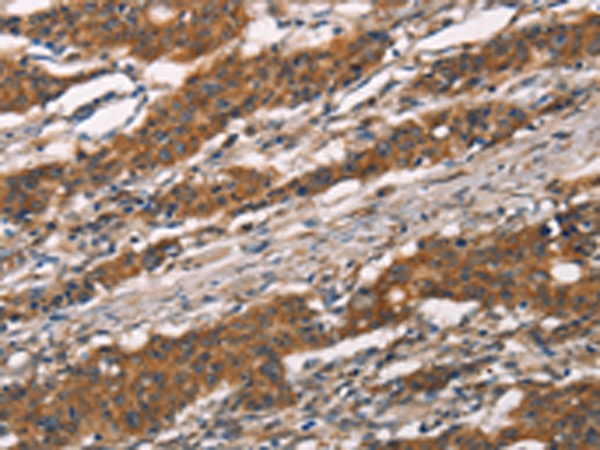

IHC positive control:

Human gastric cancer and human thyroid cancer

ELISA, IHC

IHC Recommend dilution:

25-100